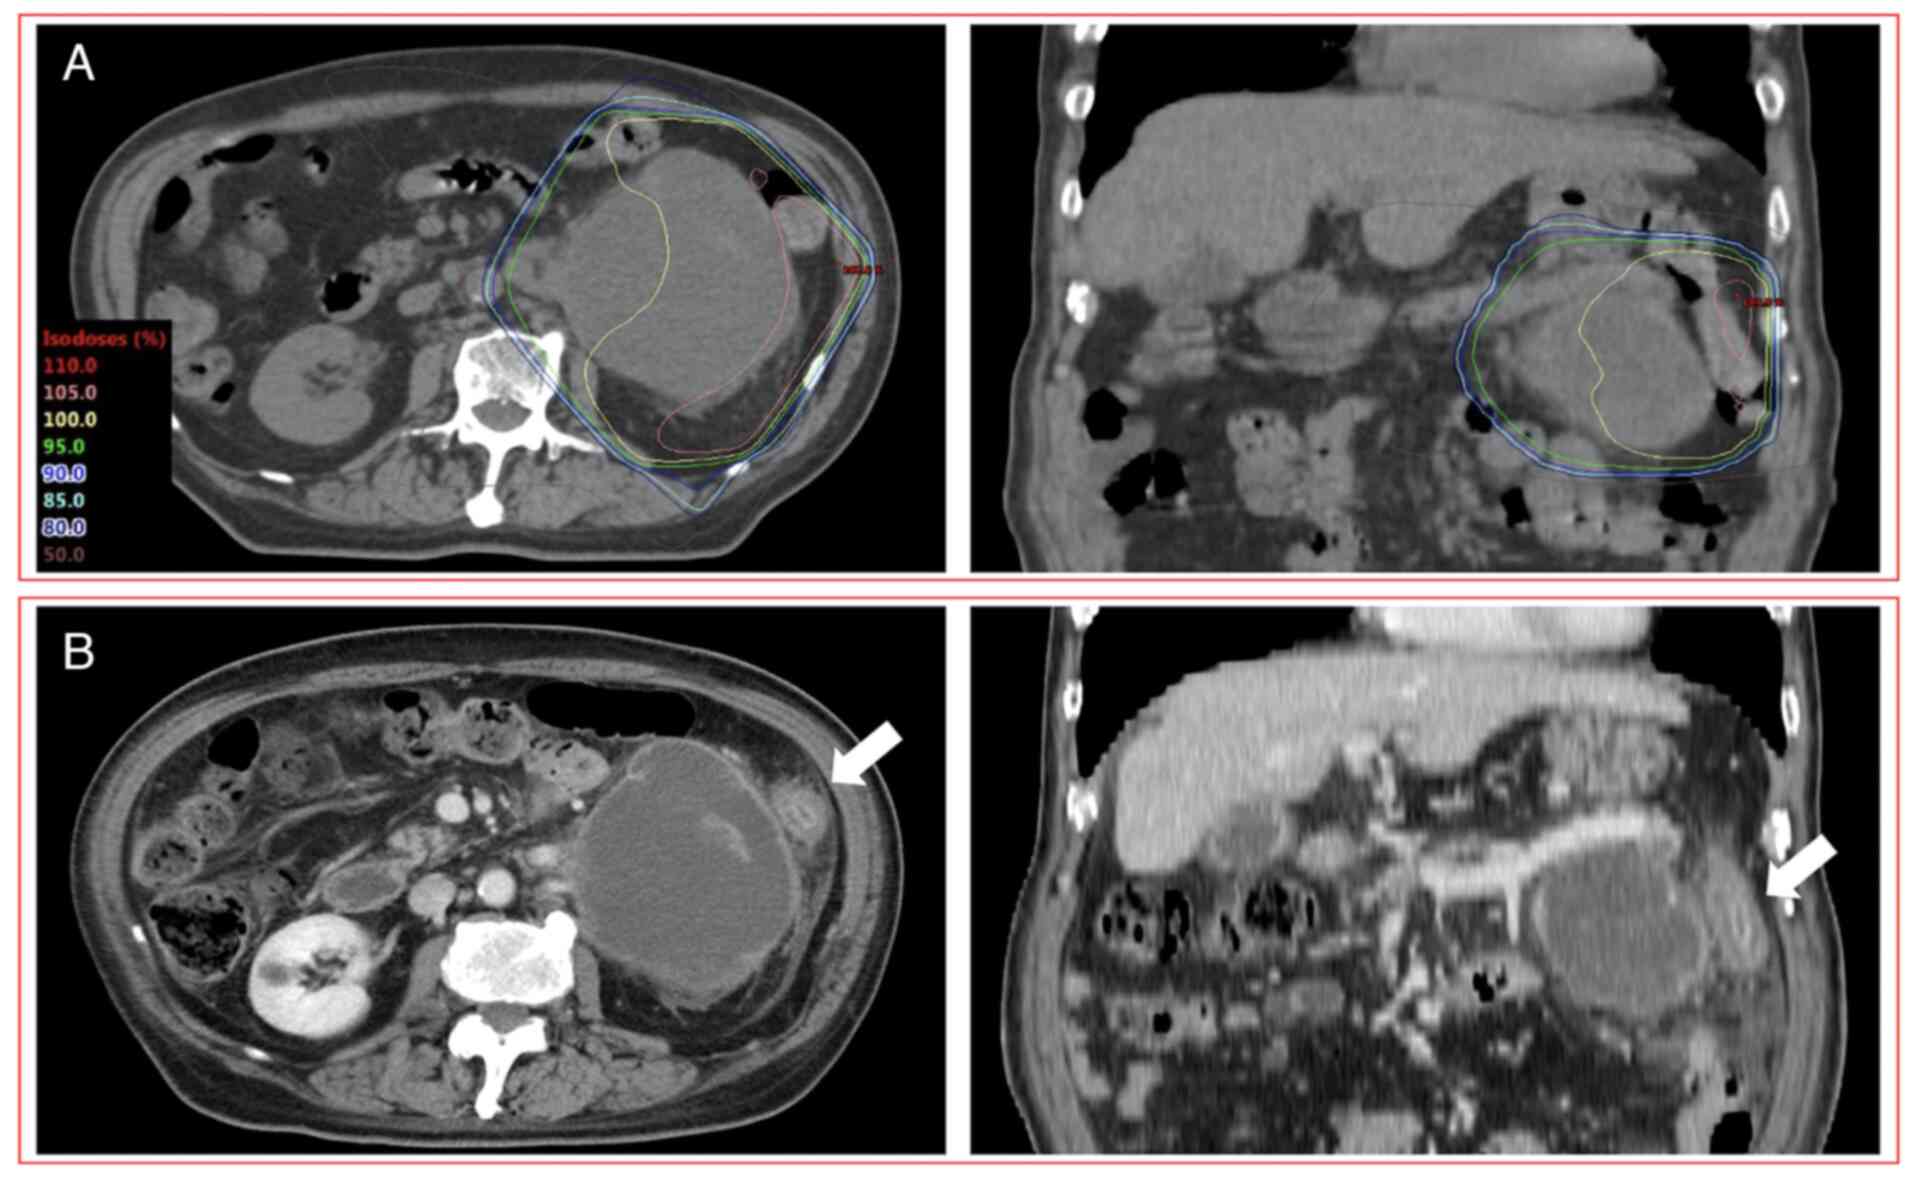

Figure 2

A patient (75 years, male) with grade 4 RIE after PRT involving the large bowel and administration of ICIs. (A) CT images displaying dose distribution of PRT to an adrenal metastasis (20 Gy in 5 fractions); (B) Contrast-enhanced CT images acquired 28 days after completion of PRT. This patient with grade 4 RIE exhibited segmental and circumferential bowel wall thickening, pericolic fat stranding and mucosal hyperenhancement in the area of the irradiated field (white arrow) as seen on CT imaging after receiving combination therapy of PRT and ICIs. Left panel showed transverse images and the right panel showed coronal images. RIE, radiation-induced enterocolitis; PRT, palliative radiotherapy; ICIs, immune checkpoint inhibitors; CT, computed tomography.

Cases with grade 2 or higher RIE

Grade 4 RIE was reported in one patient (75 years, male) who received anti-PD-L1 (atezolizumab) monotherapy with chemotherapy (carboplatin and paclitaxel) one day after completing PRT (5x4 Gy) (Fig. 2). After completing PRT, this patient had diarrhea and abdominal pain after 8 days and hematochezia after 18 days. CT images acquired 28 days after the completion of PRT indicated enterocolitis limited to the irradiated field. These symptoms were improved 49 days after the completion of PRT. However, after the third administration of anti-PD-L1 (atezolizumab) monotherapy, enterocolitis deteriorated 98 days after the completion of PRT (11 days after the third ICI administration). Eventually, as colonoscopy performed 128 days after the completion of PRT revealed erosion and angiectasis of the descending colon limited to the irradiated field without neutrophilic infiltration of the intra-epithelial compartment or formation of neutrophilic crypt abscess, this patient was diagnosed with RIE and colostomy was performed. The dose-volume parameters of D2cc, V10 and V20 of the large bowel were 21.2 Gy, 141.8 cc and 49.6 cc, respectively.